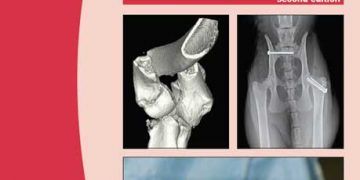

BSAVA Köpek ve Kedi kırık onarımı ve yönetimi, kırık yönetimi bu kılavuzun ilk baskısının yayınlanmasından bu yana hızla gelişmiştir. Tamamen gözden ...